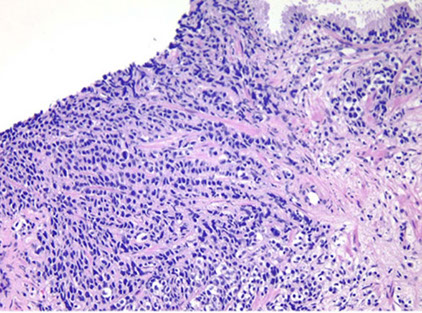

Benign Prostatic Hyperplasia (BPH)

aka nodular hyperplasia, MC urologic dz in men

The smallest nodules are have loose mesenchyme and prominent small round vessels

- some nodules can be made of only sm muscle, and may be called a leiomyoma of the prostate if it is a large symptomatic mass of sm muscle

The largest and most numerous hyperplastic nodules almost always laterally situated and occur in periurethral zone near proximal end of verumontanum

- glandular part made of small and large acini, some c papillary infoldings and projections c central fibrovascualr core (not a specific finding)

- stroma has sm muscle and fibrous tissue, which can sometimes have pallisading nuclei mimicking a neural tumor

- often lymphocytic or plasma cell infiltrates around glands

BPH